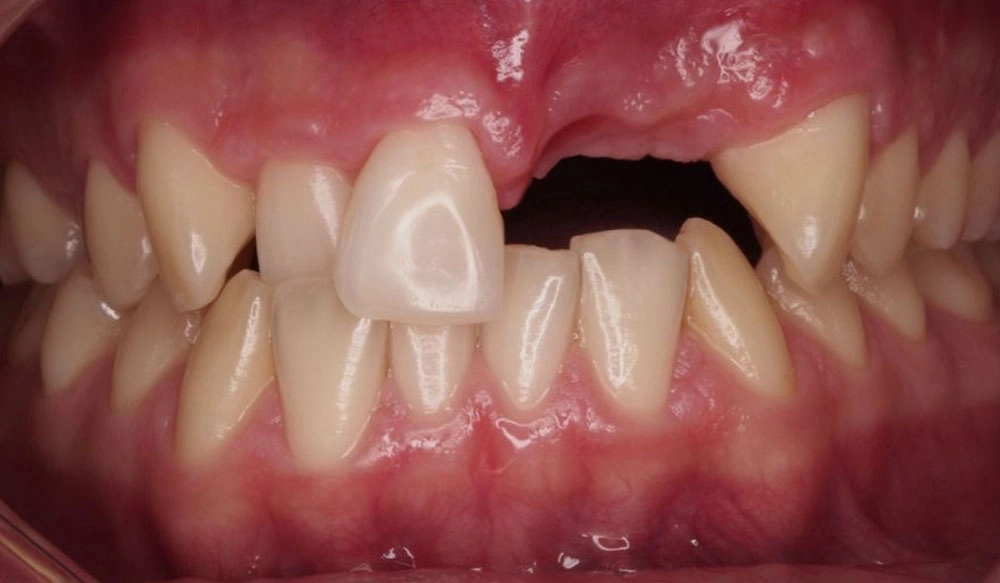

Anterior Crossbite

Anterior crossbite is the abnormal labiolingual relationship between one or more upper and lower anterior teeth, resulting in the upper teeth being positioned lingual to the lower teeth.

Patient Information:

Age: 31

Gender: Male

Invisalign Treatment Option: Invisalign Comprehensive

Total Treatment Time:

17 months